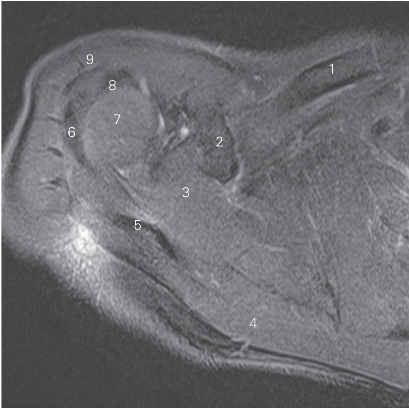

图4-8 经盂肱韧带的横断层MR T2WI FS

1 胸大肌 pectoralis major 2 锁骨 clavicle

3 喙肱肌coracobrachialis 4 后盂唇 posterior glenoid labium

5 肩胛下肌 subscapularis 6 肩胛骨 scapula

7 冈下肌 infraspinatus 8 关节盂 glenoid cavity

9 肩关节 shoulder joint

10 肱二头肌长头腱 tendon of long head of biceps brachii

11 三角肌 deltoid